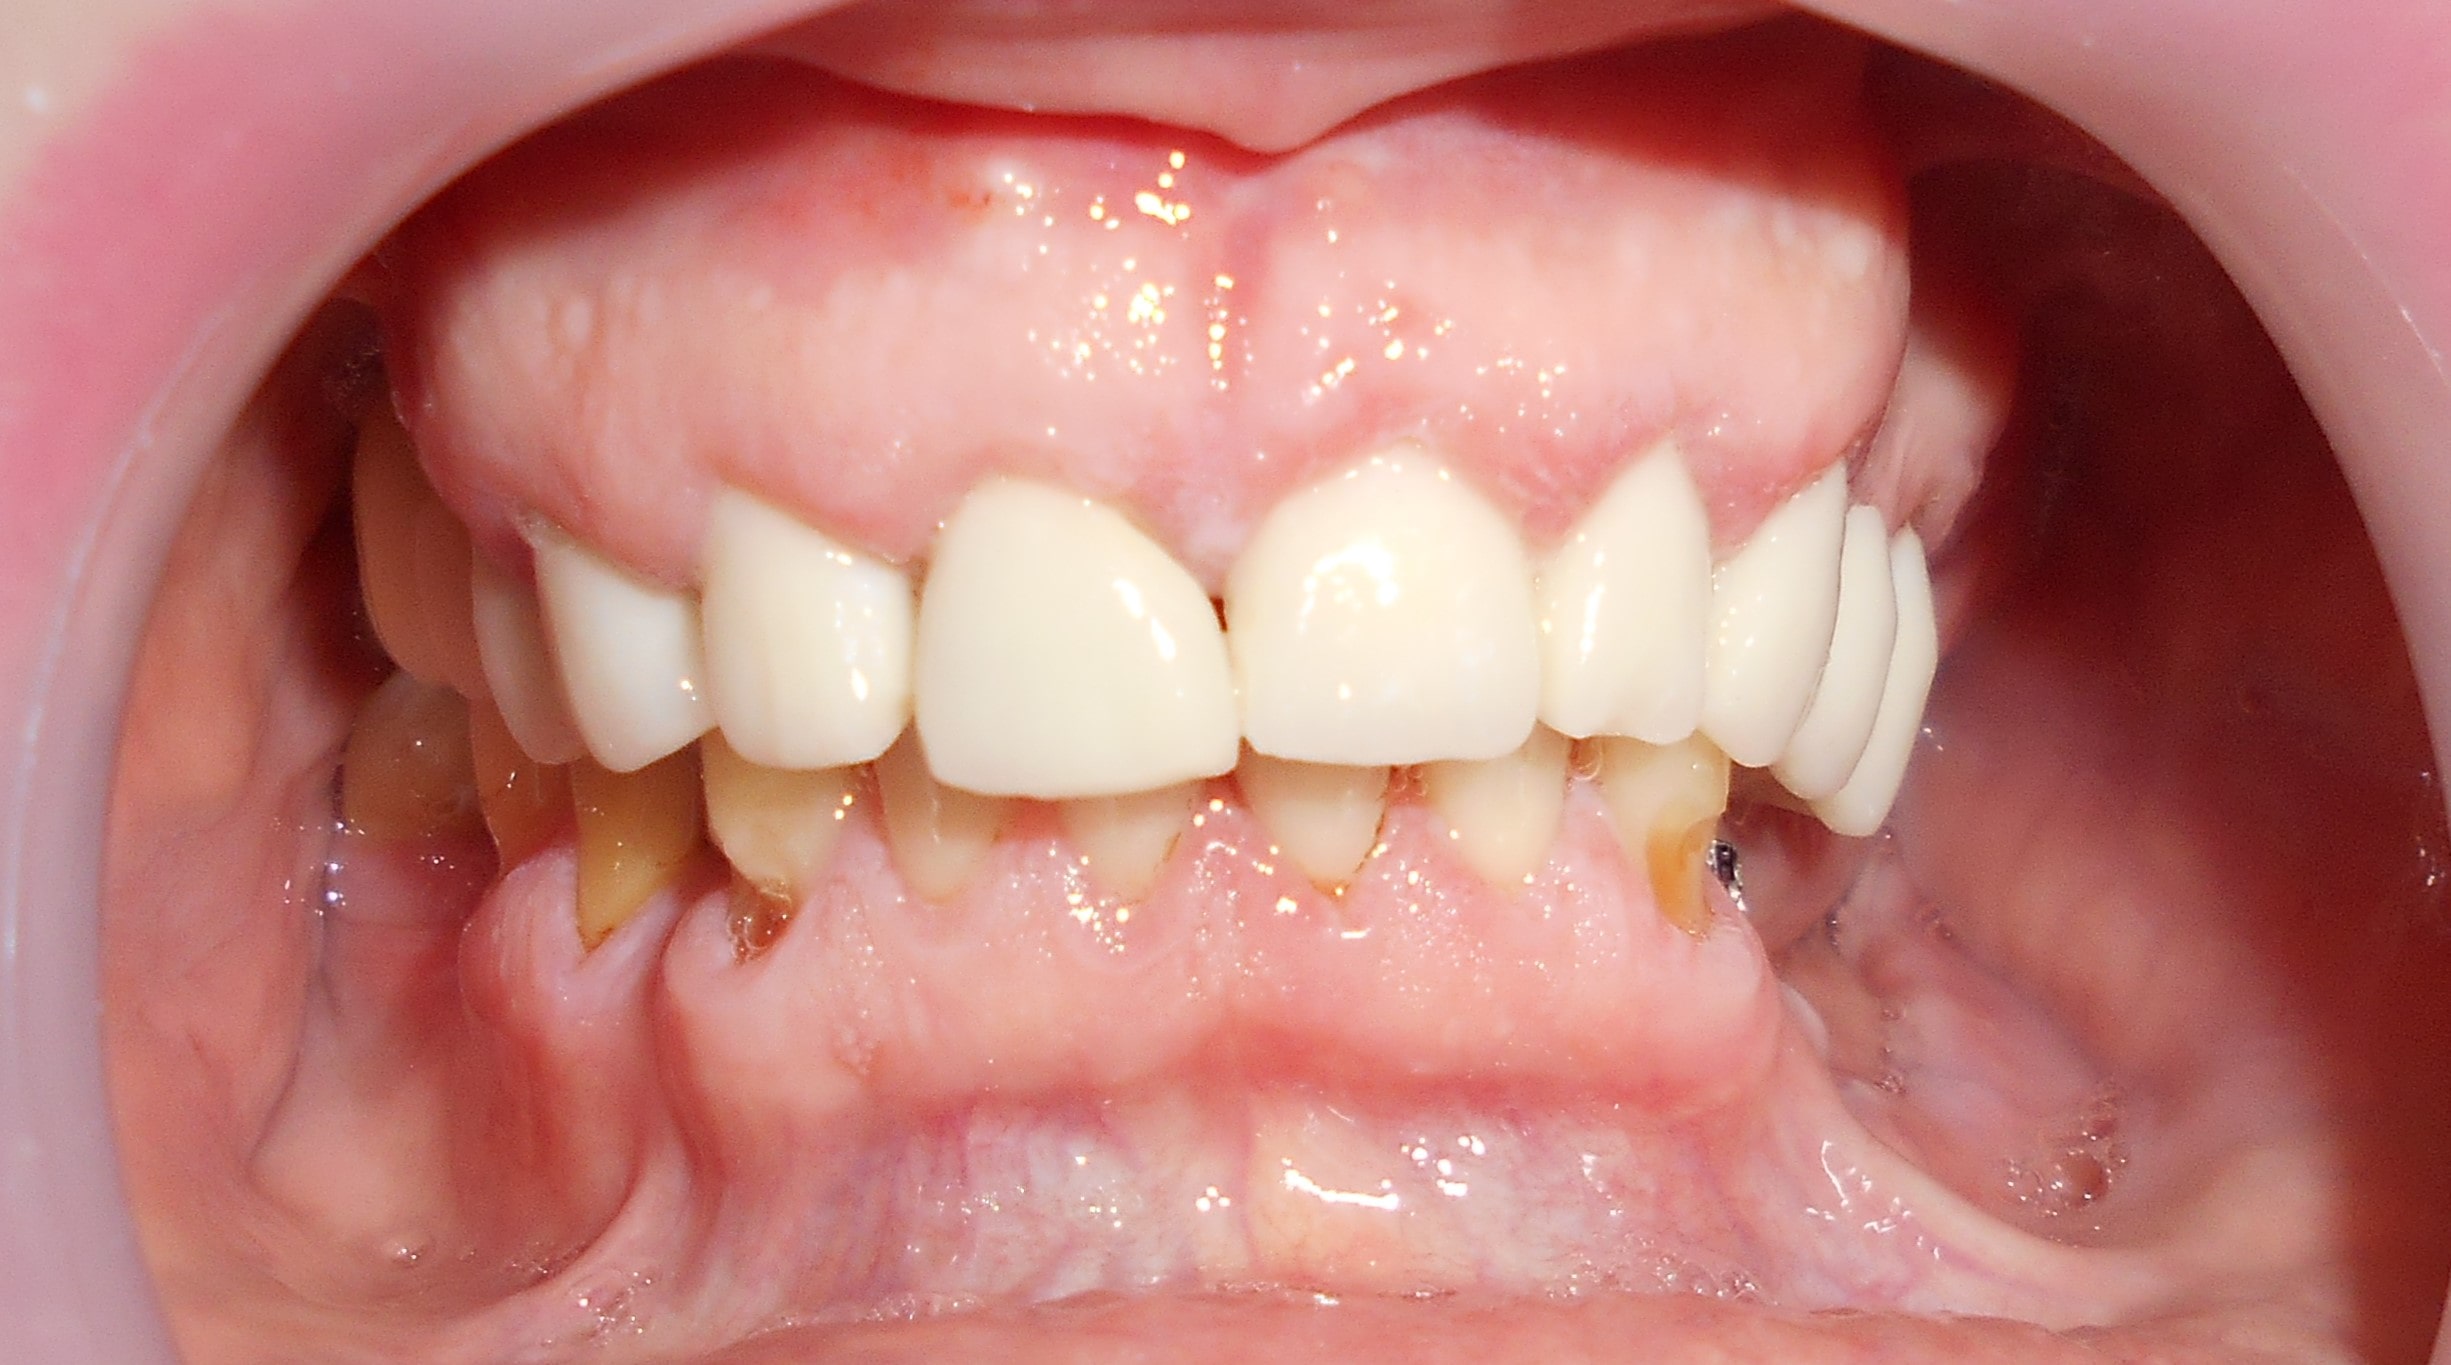

Pacijent iz Nemačke, kod koga smo estetsko i funkcionalno zbrinjavanje rešili cirkonijum keramičkim krunicama sa ugradnjom kratkih implantata u donjoj vilici zbog smanjene visine kosti, a u gornjoj vilici na levoj strani odmah nakon vađenja zuba je ugrađen standardni implantata na mesto izvađenog zuba i ugrađen je tuberopterigoidni implantat da se ne bi radila komplikovana sinus lift procedura koja bi produžila vreme završetka rada na godinu i više dana. Rad uspešno završen i pacijent nema nikakvih problema već pet godina.